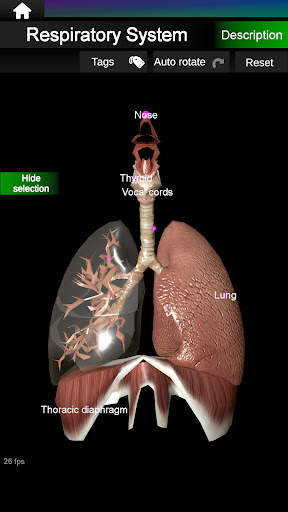

* Ademhalingssysteem, inclusief de luchtpijp, bronchiën, longen en een animatie van dit systeem.

* Gemakkelijk te openen en te navigeren (zoom, 3D-rotatie).

* Verberg of toon informatie.

* Beschrijvingen van elk orgel.